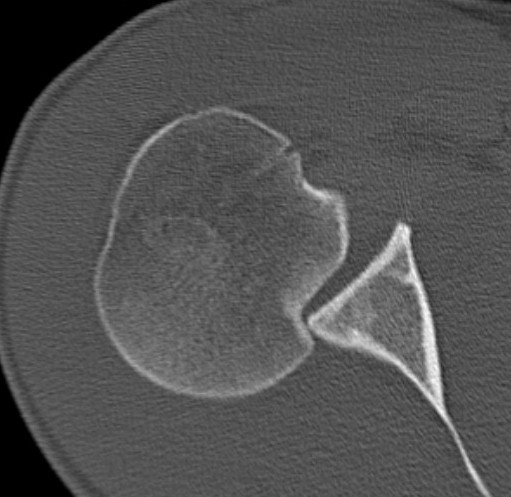

CT scan

Confirms dislocation

Reverse Hill Sachs

Humeral head defect

- caused by impaction of anterior humeral head on posterior glenoid

- intra-articular

- measured as a percentage of the articular surface

Lesser tuberosity fractures

Posterior glenoid fractures / bony bankart